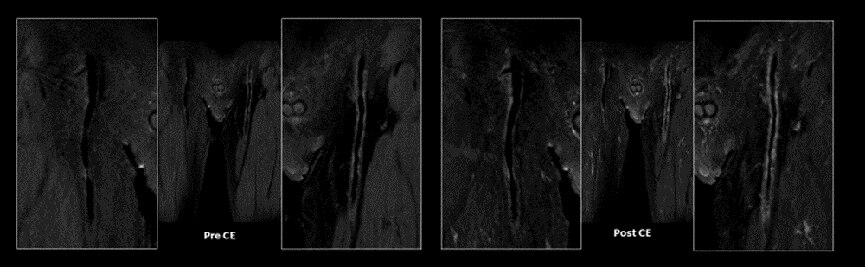

Figure. 6

下腿部のMSDE併用Cube T1。造影前撮像で血管壁のプラークを確認した。造影剤投与後の撮像では血管壁の信号増強効果が確認された。